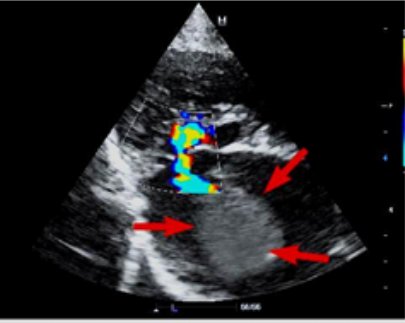

Эхокардиография (рис. 3–5). Данный метод позволяет выявить основное заболевание сердца. Также можно выявить изменение кровотока и замедленное прохождение крови в ушке или в полости левого предсердия посредством импульсно-волнового доплера. У некоторых кошек тромб, формирующийся (в виде облака) или зрелый, можно увидеть в левом предсердии.